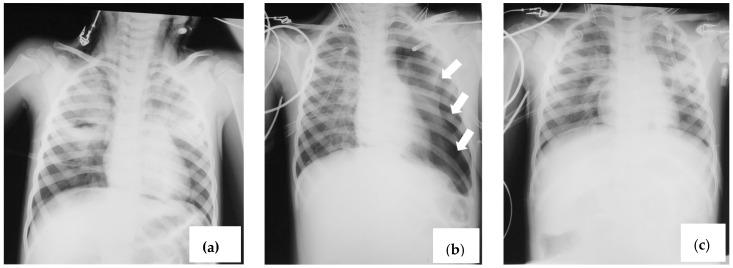

In this study, we present four cases of Human Bocavirus (HBoV) infection in children aged between 1 month and 4 years. Among these cases, two siblings were hospitalized with similar symptoms. Among the four pediatric cases of patients with HBoV infection, three were associated with acute respiratory failure and spontaneous pneumothorax, and two of these presented with subcutaneous emphysema. The presented patients were young children, aged between 1 month and 4 years, two of whom were siblings, suggesting a possible intrafamilial transmission of HBoV1 infection. These cases highlight the importance of considering HBoV as a differential diagnosis in pediatric patients with respiratory and gastrointestinal symptoms. Early recognition and appropriate medical care are important in treating HBoV infection in young children.

在本研究中,我们报告了 4 例年龄在 1 个月至 4 岁之间的儿童感染 Human Bocavirus(HBoV)的病例。其中,2 名兄弟姐妹出现了类似的症状而住院治疗。在这 4 例 HBoV 感染的儿科病例中,有 3 例与急性呼吸衰竭和自发性气胸有关,其中 2 例伴有皮下气肿。这些患儿年龄均较小,年龄在 1 个月至 4 岁之间,其中 2 例为兄弟姐妹,提示 HBoV1 感染可能存在家族内传播。这些病例强调了在有呼吸道和胃肠道症状的儿科患者中,将 HBoV 视为鉴别诊断的重要性。早期识别和适当的医疗护理对于治疗幼儿的 HBoV 感染非常重要。